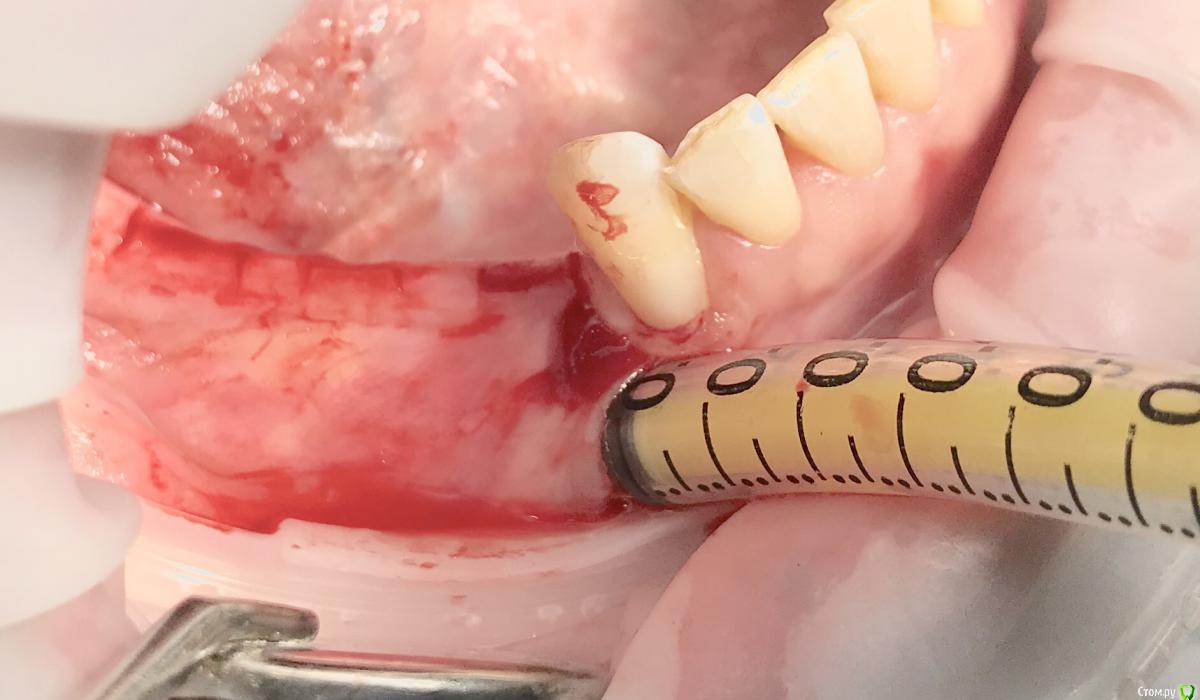

колесников Опубликовано 25 ноября, 2018 Поделиться Опубликовано 25 ноября, 2018 Фото для примера,из разряда было-стало. Обычно рядовые случаи не фотографирую,но тут решил запечатлеть. Тоннель плюс имплантация,делал впервые. Примерно понятно как узкий гребень превращается в широкую сосиску. 2 Ссылка на комментарий

колесников Опубликовано 26 ноября, 2018 Поделиться Опубликовано 26 ноября, 2018 Скажите плз, импланты одномоментно с графтингом, если да , то какой шаблон, по КТ?Да,тут одномоментно. Хорошо это или нет,будет ли все удачно-не могу сказать,делал так впервые,главное понять как это работает.Делать отсроченно мне уже скучно. Повторять не рекомендую. Шаблон не использовал,он тут не поможет,гребень 2мм. Ссылка на комментарий

колесников Опубликовано 26 ноября, 2018 Поделиться Опубликовано 26 ноября, 2018 Скальпель 15С,пинцет ,серповидная гладилка,викрил. Учусь у всех по немногу. Лучший учитель опыт. 1 Ссылка на комментарий